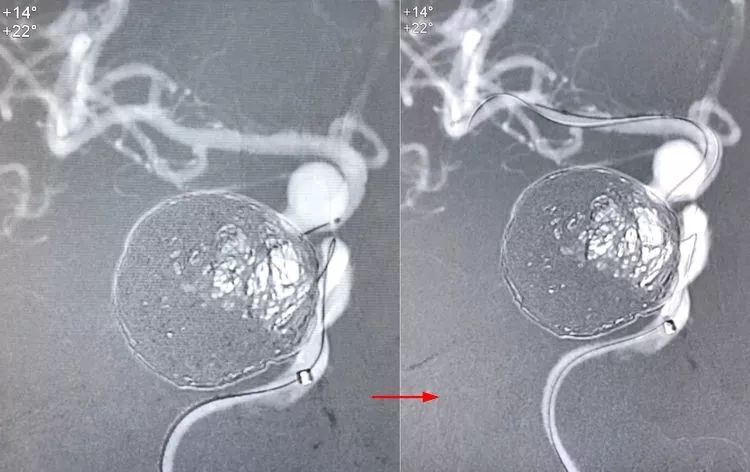

应用Synchro-14微导丝(300cm)交换技术,撤离Echelon-10微导管,交换入T-track支架导管,经支架导管输送Tubridge®密网支架(4.5×45mm),支架头端锚定于右侧大脑中动脉起始部。

完全释放Tubridge®密网支架。

术后右颈内动脉正侧位造影显示:右大脑前动脉不显影,考虑为血流动力学因素所致。

左侧颈内动脉床突段及左侧大脑中动脉M1段也有多发动脉瘤,等待三期治疗。